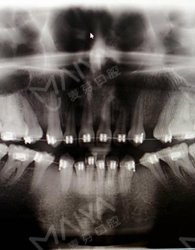

終於又等到週末啦! 這一次作為患者來到麥芽,進門後客服笑盈盈的給我開門,然後填了單子,就有專人帶我去見麥芽的主任了,主任和照片上一樣平易近人,讓我和醫生的距離一下子就拉近了,耐心的聽了我的苦惱。 為了看一下我的牙齒,客服帶著我還拍了片,這是我在之前矯正的時候沒有的環節。 看到電腦上顯示的自己的牙齒,對這種高科技的東西著實驚了一下,相信很多人和我一樣都覺得矯牙就是醫生看一下,就開始戴牙套了,但是這一刻我終於明白了,矯牙並不是你以為,科技設備醫生這些都很重要。

張主任指著片子說,牙齒錯過了最好的矯牙年齡,而且又矯牙失敗,我的屬於疑難矯正了,但是還是可以矯正好的! 然後為了減輕我的痛苦,讓我繼續戴現在的牙套,但是要分階段調整一下,我非常開心感覺牙齒還有救,當天醫生給我調整好之後,牙齒就舒服了很多,我的心情也是多雲轉晴!!!